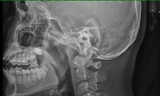

Ngay sau khi tiếp nhận bệnh nhi, các BS đã tiến hành thăm khám và chỉ định chụp X-Quang, kết quả cho thấy có hình ảnh dị vật giống đồng xu nằm trong 1/3 trên thực quản.

Bàng hoàng phát hiện đồng xu nằm trong thực quản bé gái 5 tuổi ảnh 1Ảnh chụp X-Quang dị vật